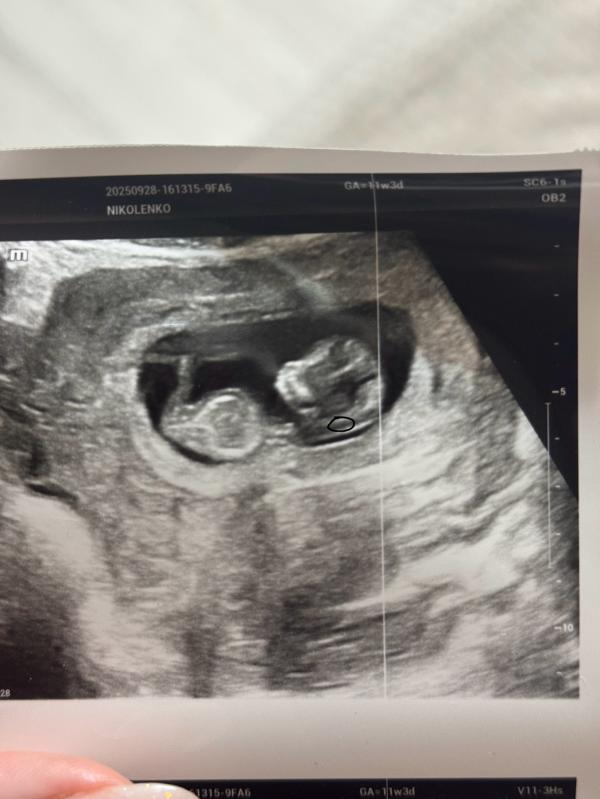

А твп это вот эта часть?

Да, похоже, что она

Это толщина воротникового пространства, шейка

участок между кожным покровом плода и тканями

Нет, ниже

Черное где